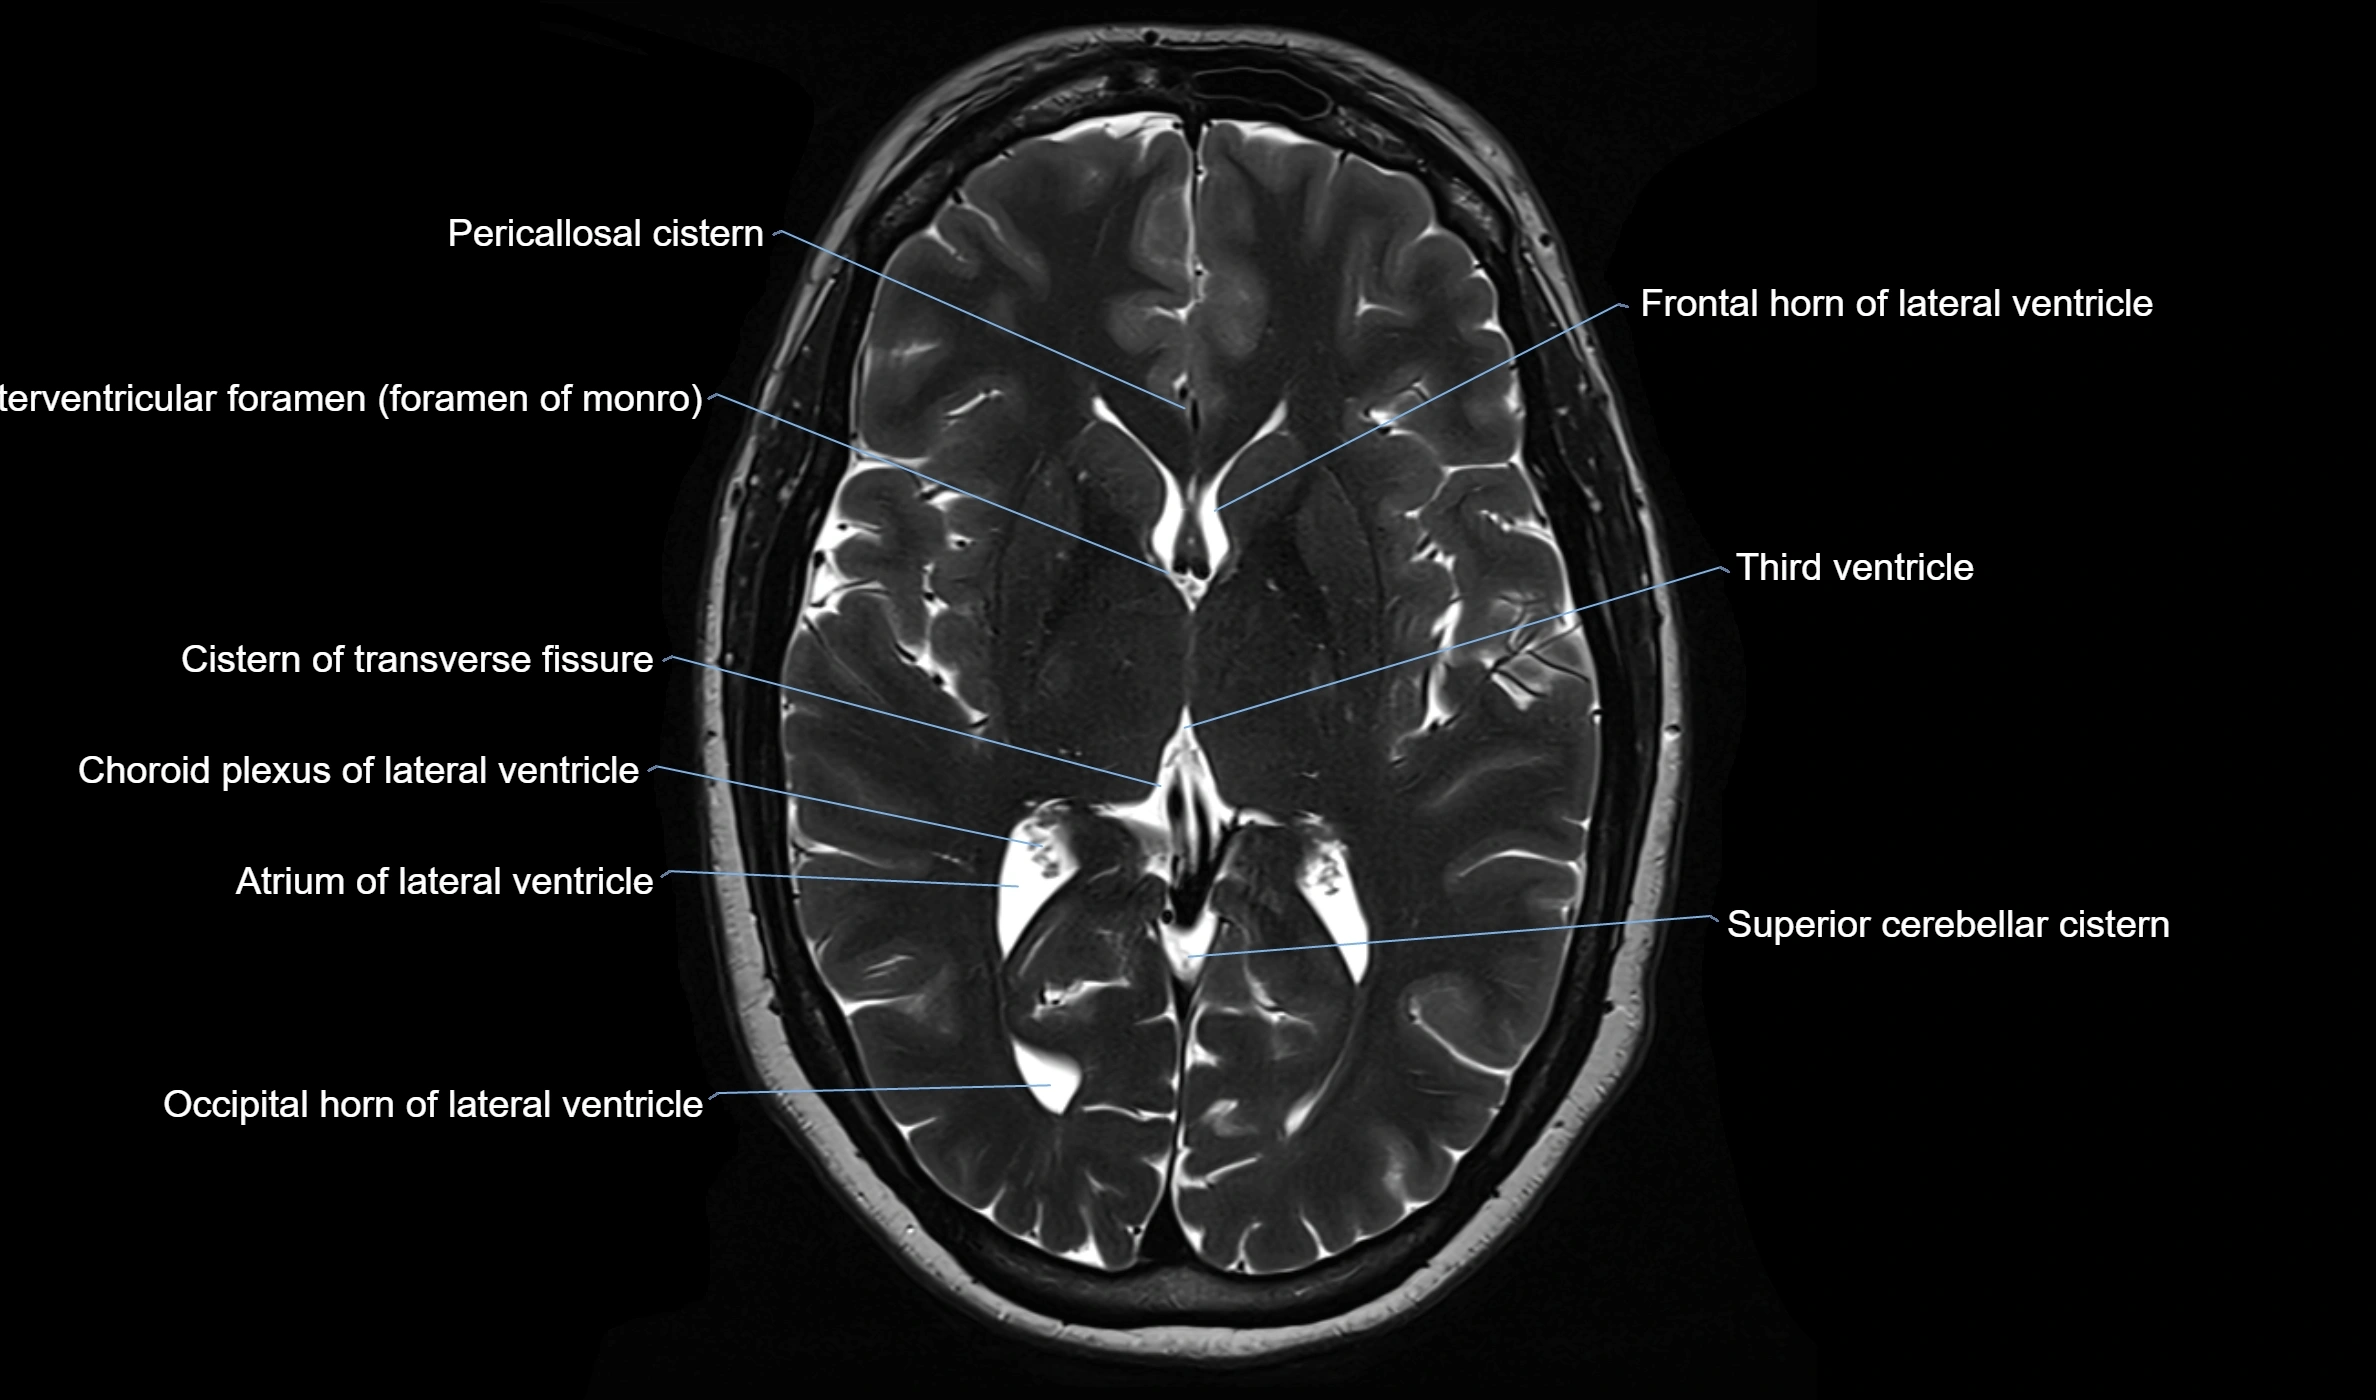

CT image

image